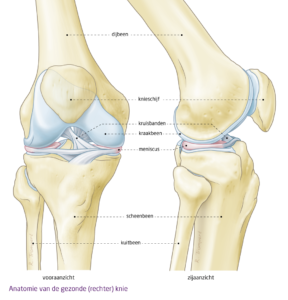

Wat is een meniscus?

Een meniscus is een stug kraakbenig schijfje tussen het onderbeen en bovenbeen. Zowel aan de binnenkant als de buitenkant van je knie heb je een meniscus, dus in totaal heb je er vier!

Dit schijfje, ook wel beschreven als halve maanvormig, begeleidt de beweging van je knie tijdens buigen en strekken van je knie. Hiermee verzorgt de meniscus de stabiliteit van de knie en verdeelt je gewicht zich gelijkmatig over het kraakbeen van je boven- en onderbeen.